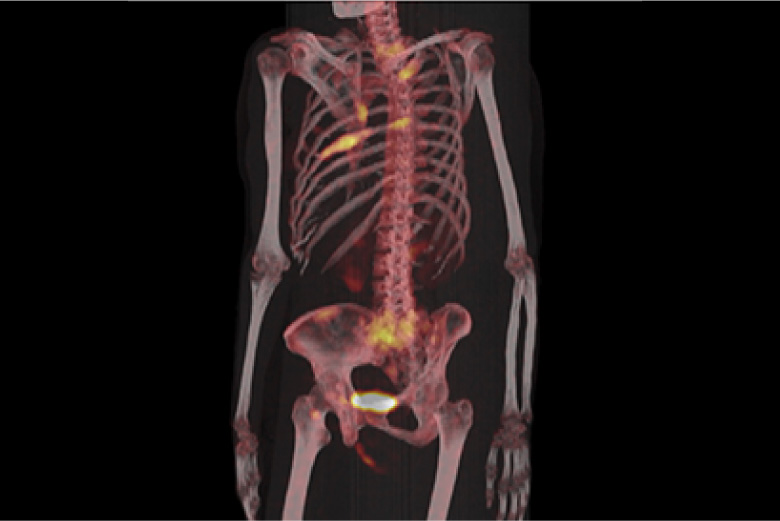

PET検査

PET検査とは、「陽電子放射断層撮影」という意味で、ポジトロン・エミッション・トモグラフィー(Positron Emission Tomography)の略です。当院の検査装置は、PETとCTを同時に短時間で撮影ができます。PETではがん細胞の活動状況を知ることを得意とし、CTでは臓器の形をしっかりと映し出すことを得意とします。その二つの画像を重ね合わせてみることにより、正確な診断を行うことができます。全身のがん、脳、心臓などの病気の診断に有効です。

RI(核医学検査)

RI検査(核医学検査)は、ごく微量の放射性物質(ラジオアイソトープ:RI)を含む薬を用いて病気を診断する検査です。この放射性医薬品を注射、吸入などにより体内に取り込みます。体内に取り込まれると、特定の臓器(骨や腫瘍など)に集まりそこから放出される放射線(γ線)をガンマカメラで測定し、その分布を画像化します。

この検査の特徴は臓器の位置や大きさの他に機能が分かるというところです。

心筋血流シンチ 脳血流シンチ 骨シンチ 甲状腺シンチ 腫瘍シンチなど

骨シンチ

転移性骨腫瘍